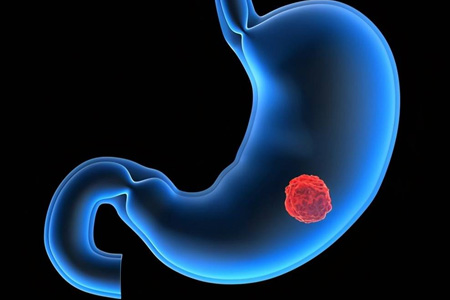

胃間質瘤是一種在胃腸道内層組織中形成的腫瘤。它起源于胃壁内的間質細胞,這些細胞通常是負責支持胃腸道組織結構的細胞。胃間質瘤通常是一種緩慢生長的腫瘤,大多數情況下是良性的,但在少數情況下也可能是惡性的。

确診胃間質瘤通常需要進行多種檢查,包括胃鏡檢查、超聲波檢查以及組織活檢等。治療方案取決于腫瘤的性質和患者的整體健康狀況。小型、良性的胃間質瘤可能隻需定期監測。大型或有症狀的腫瘤可能需要手術切除。對于惡性腫瘤,通常會采用放療、化療或靶向藥物治療等。